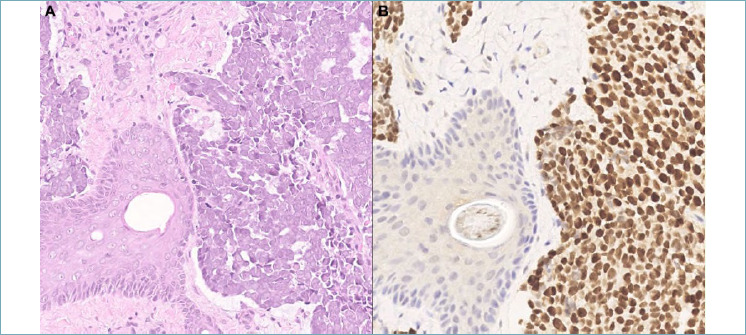

Pathology is pivotal in diagnosing skin tumors, and the precision of diagnosis is crucial to devise customized treatment plans and enhance patient care in dermatology. The latest edition of the World Health Organization's classification of skin tumors serves as a comprehensive compendium, summarizing and categorizing all recent advancements in both anatomical-pathological and molecular aspects of cutaneous neoplasms. Several relevant advances have been introduced and new entities have been described. While the fundamental structure of the classification remains unchanged, notable additions include three new sections aimed at providing a more exhaustive description of skin lesions: nail unit tumors, skin metastases, and genetic tumor syndromes associated with skin malignancies. Recent strides in molecular pathology have led to significant breakthroughs in decoding the underlying mechanisms of various skin tumors, ranging from adnexal neoplasms to hematolymphoid neoplasms, soft tissue tumors, and melanocytic lesions. Of particular importance is the evolution in our understanding of melanocytic neoplasms, with the introduction of the term "melanocytoma" reserved for lesions exhibiting "intermediate" biological behavior and characterized by specific molecular mutations. The pathologic diagnosis process integrates morphological, immunohistochemical, and molecular features, playing a crucial role in clinical decision-making. The WHO classification serves as a valuable tool in promoting multidisciplinarity in the management of cutaneous neoplasms with the aim of translating novel pathological discoveries into more effective treatments. This review aims to distill the major updates introduced by the new classification, providing a synthesis of the latest scientific insights.